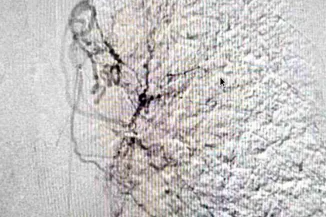

「喷射性咯血!医生临危不乱,微创介入化险为夷」